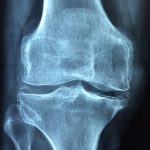

Artrose no Joelho: Como a Fisioterapia Domiciliar Pode Aliviar seus Sintomas

Introdução: A artrose no joelho é uma condição degenerativa que afeta milhões de pessoas em todo o mundo. Essa doença crônica pode causar dor, rigidez e limitação dos movimentos, afetando…

Condromalácia Patelar

Introdução A condromalácia patelar é uma das condições mais comuns que afeta o joelho, especialmente em atletas e indivíduos que praticam atividades físicas de alto impacto. Trata-se de uma patologia…